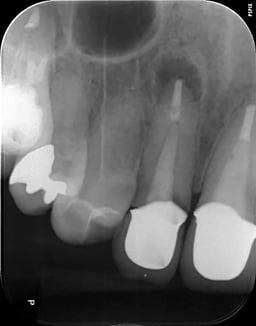

#顕微鏡下での根管治療について

支台築造(コア)の重要性